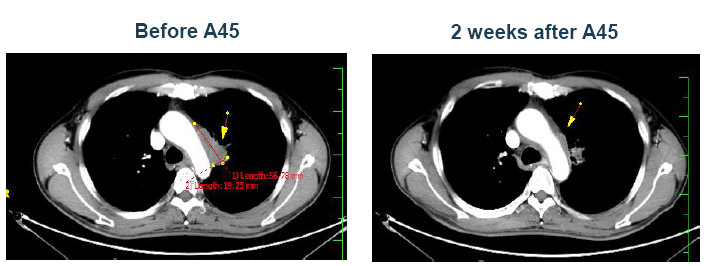

案例三

患者男性,63岁。中心型肺癌。

确诊时肿瘤已经压迫喉管神经,造成声音嘶哑、咳嗽,已失去手术机会,拒绝放化疗,半年后,病情恶化,肿瘤从3cm增至6cm。患者家属遍访全国各大医院,最后找到全球肿瘤医生网,经过多学科顶尖癌症专家会诊,制定A45治疗方案。治疗2周后,肿瘤从6厘米降到2厘米内,咳嗽消失,声音嘶哑也有明显好转,3个月后再次复查,肿瘤完全控制,病人的目前精神状况也非常乐观。 图片显示左肺中央型肺癌伴肺门淋巴结转移,病理明确低分化鳞癌伴神经内分泌癌分化,肿瘤大小约4.6*4.0*4.3cm,两次A45肿瘤治疗后复查肿瘤大幅缩小,代谢降低。目前患者身体状况良好。